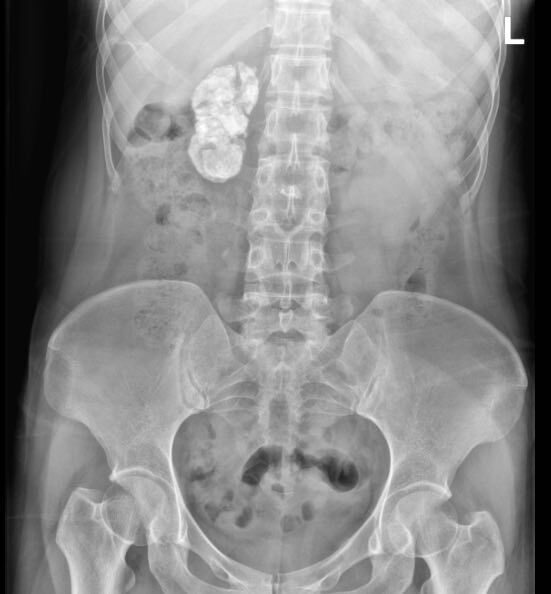

24岁的韦先生平时身体健康,没发现什么大毛病,没想到在公司组织的一次体检中竟然发现自己的右肾大面积钙化,丧失功能。而原因竟然是5岁时得的一次肺结核!为了确保左肾功能不受影响,最终,韦先生选择了切除右肾。

泌尿外科庞俊主任告诉他,他的右肾完全钙化了,临床上叫“肾自截”,多由肾结核引起。原因在于结核侵蚀导致肾盂输尿管梗阻,肾脏在发生干酪样坏死后广泛钙化。

结核杆菌随血运率先进入肾皮质,形成微结核病灶,称为“病理性肾结核”,若结核进一步进展侵犯髓质集合系统,则可出现血尿、尿频、尿急等症状,称为“临床肾结核”。早期典型影像学表现为肾盂肾盏虫蚀样改变,末期会导致肾积水、肾广泛钙化、输尿管钙化、膀胱挛缩、对侧肾积水,严重者双肾功能丢失,引起尿毒症。

对于韦先生来说,自截的右肾已经失去了功能,为避免影响到左肾,韦先生最终选择了切除右肾。经过手术治疗,韦先生已康复出院,复查发现左肾状况良好。